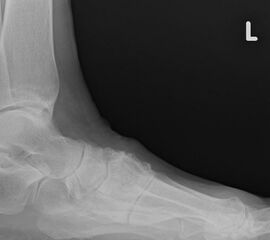

• konventionelle Röntgenbilder mit Belastung im Stehen a. p. und seitlich, ggf. schräg (Abb. 9, 10 und 11).

Es gibt neben der Möglichkeit mit der in situ TMT II, III Arthrodese auch die Möglichkeit Fehlstellungen wie den Pes metatarsus adductus zu adressieren (Abb. 9 und Abb. 24 zeigen das prä- und postoperative Röntgenbild eines Patienten mit Pes adductus Korrektur).